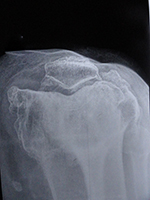

OA - CASE 1

DSC01384

DSC01385

Imm psop lt

Imm psop ap

DSC01386

DSC01383

Imm psop